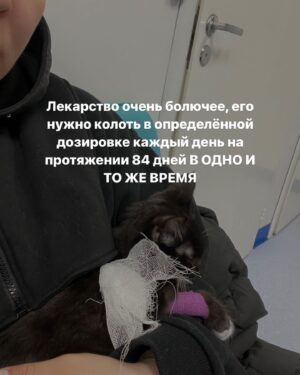

Caption : Про наших «блох», их болезнь и про классы от нас с @baturo_ Друзья, мы в конце января с Андреем взяли 3х котят из приюта. Прелестные, ласковые создания. К сожалению, двое из них заболели FIP (об этом рассказывала неделю назад, можно прочесть в карусели или в актуальном) Мы с Андреем уже очень сильно их любим, сдаваться не намерены. Четко и уверенно настроены на лучшее. Поэтому мы организовываем классы в Санкт-Петербурге 22 апреля‼️, все средства от которых пойдут на лечение наших блох, Нео и Абу. ⚫️22 апреля 15.00-17.00- Андрей Батуро (изоляция, виды) 17.00-19.00- Баина (партерная техника, основы безопасности в партере, грамотное распределение веса) ⚫️Стоимость: 1 класс-1500 руб 2 класса-2500 руб Место проведения: Jonathan, измайловский проспект, 2, зал 14 (вход со стороны измайловского проспекта) Код от домофона Внизу #1962 Наверху 2703# Проведите время с пользой для себя и помогите поправить здоровье двум маленьким котятам) Для записи пишите в директ) Мы очень будем рады видеть всех, а также просим максимально помочь с распространением этого поста, чтобы больше человек могли увидеть его)) P.S пользуясь случаем, хочу поблагодарить всех неравнодушных, кто просто захотел помочь монеткой🙏🏻🙏🏻 Это до слез ценно!Likes : 1330

Caption : Про наших «блох», их болезнь и про классы от нас с @baturo_ Друзья, мы в конце января с Андреем взяли 3х котят из приюта. Прелестные, ласковые создания. К сожалению, двое из них заболели FIP (об этом рассказывала неделю назад, можно прочесть в карусели или в актуальном) Мы с Андреем уже очень сильно их любим, сдаваться не намерены. Четко и уверенно настроены на лучшее. Поэтому мы организовываем классы в Санкт-Петербурге 22 апреля‼️, все средства от которых пойдут на лечение наших блох, Нео и Абу. ⚫️22 апреля 15.00-17.00- Андрей Батуро (изоляция, виды) 17.00-19.00- Баина (партерная техника, основы безопасности в партере, грамотное распределение веса) ⚫️Стоимость: 1 класс-1500 руб 2 класса-2500 руб Место проведения: Jonathan, измайловский проспект, 2, зал 14 (вход со стороны измайловского проспекта) Код от домофона Внизу #1962 Наверху 2703# Проведите время с пользой для себя и помогите поправить здоровье двум маленьким котятам) Для записи пишите в директ) Мы очень будем рады видеть всех, а также просим максимально помочь с распространением этого поста, чтобы больше человек могли увидеть его)) P.S пользуясь случаем, хочу поблагодарить всех неравнодушных, кто просто захотел помочь монеткой🙏🏻🙏🏻 Это до слез ценно!Likes : 1330

Caption : Про наших «блох», их болезнь и про классы от нас с @baturo_ Друзья, мы в конце января с Андреем взяли 3х котят из приюта. Прелестные, ласковые создания. К сожалению, двое из них заболели FIP (об этом рассказывала неделю назад, можно прочесть в карусели или в актуальном) Мы с Андреем уже очень сильно их любим, сдаваться не намерены. Четко и уверенно настроены на лучшее. Поэтому мы организовываем классы в Санкт-Петербурге 22 апреля‼️, все средства от которых пойдут на лечение наших блох, Нео и Абу. ⚫️22 апреля 15.00-17.00- Андрей Батуро (изоляция, виды) 17.00-19.00- Баина (партерная техника, основы безопасности в партере, грамотное распределение веса) ⚫️Стоимость: 1 класс-1500 руб 2 класса-2500 руб Место проведения: Jonathan, измайловский проспект, 2, зал 14 (вход со стороны измайловского проспекта) Код от домофона Внизу #1962 Наверху 2703# Проведите время с пользой для себя и помогите поправить здоровье двум маленьким котятам) Для записи пишите в директ) Мы очень будем рады видеть всех, а также просим максимально помочь с распространением этого поста, чтобы больше человек могли увидеть его)) P.S пользуясь случаем, хочу поблагодарить всех неравнодушных, кто просто захотел помочь монеткой🙏🏻🙏🏻 Это до слез ценно!Likes : 1330

Caption : Про наших «блох», их болезнь и про классы от нас с @baturo_ Друзья, мы в конце января с Андреем взяли 3х котят из приюта. Прелестные, ласковые создания. К сожалению, двое из них заболели FIP (об этом рассказывала неделю назад, можно прочесть в карусели или в актуальном) Мы с Андреем уже очень сильно их любим, сдаваться не намерены. Четко и уверенно настроены на лучшее. Поэтому мы организовываем классы в Санкт-Петербурге 22 апреля‼️, все средства от которых пойдут на лечение наших блох, Нео и Абу. ⚫️22 апреля 15.00-17.00- Андрей Батуро (изоляция, виды) 17.00-19.00- Баина (партерная техника, основы безопасности в партере, грамотное распределение веса) ⚫️Стоимость: 1 класс-1500 руб 2 класса-2500 руб Место проведения: Jonathan, измайловский проспект, 2, зал 14 (вход со стороны измайловского проспекта) Код от домофона Внизу #1962 Наверху 2703# Проведите время с пользой для себя и помогите поправить здоровье двум маленьким котятам) Для записи пишите в директ) Мы очень будем рады видеть всех, а также просим максимально помочь с распространением этого поста, чтобы больше человек могли увидеть его)) P.S пользуясь случаем, хочу поблагодарить всех неравнодушных, кто просто захотел помочь монеткой🙏🏻🙏🏻 Это до слез ценно!Likes : 1330

Caption : Про наших «блох», их болезнь и про классы от нас с @baturo_ Друзья, мы в конце января с Андреем взяли 3х котят из приюта. Прелестные, ласковые создания. К сожалению, двое из них заболели FIP (об этом рассказывала неделю назад, можно прочесть в карусели или в актуальном) Мы с Андреем уже очень сильно их любим, сдаваться не намерены. Четко и уверенно настроены на лучшее. Поэтому мы организовываем классы в Санкт-Петербурге 22 апреля‼️, все средства от которых пойдут на лечение наших блох, Нео и Абу. ⚫️22 апреля 15.00-17.00- Андрей Батуро (изоляция, виды) 17.00-19.00- Баина (партерная техника, основы безопасности в партере, грамотное распределение веса) ⚫️Стоимость: 1 класс-1500 руб 2 класса-2500 руб Место проведения: Jonathan, измайловский проспект, 2, зал 14 (вход со стороны измайловского проспекта) Код от домофона Внизу #1962 Наверху 2703# Проведите время с пользой для себя и помогите поправить здоровье двум маленьким котятам) Для записи пишите в директ) Мы очень будем рады видеть всех, а также просим максимально помочь с распространением этого поста, чтобы больше человек могли увидеть его)) P.S пользуясь случаем, хочу поблагодарить всех неравнодушных, кто просто захотел помочь монеткой🙏🏻🙏🏻 Это до слез ценно!Likes : 1330

Caption : Про наших «блох», их болезнь и про классы от нас с @baturo_ Друзья, мы в конце января с Андреем взяли 3х котят из приюта. Прелестные, ласковые создания. К сожалению, двое из них заболели FIP (об этом рассказывала неделю назад, можно прочесть в карусели или в актуальном) Мы с Андреем уже очень сильно их любим, сдаваться не намерены. Четко и уверенно настроены на лучшее. Поэтому мы организовываем классы в Санкт-Петербурге 22 апреля‼️, все средства от которых пойдут на лечение наших блох, Нео и Абу. ⚫️22 апреля 15.00-17.00- Андрей Батуро (изоляция, виды) 17.00-19.00- Баина (партерная техника, основы безопасности в партере, грамотное распределение веса) ⚫️Стоимость: 1 класс-1500 руб 2 класса-2500 руб Место проведения: Jonathan, измайловский проспект, 2, зал 14 (вход со стороны измайловского проспекта) Код от домофона Внизу #1962 Наверху 2703# Проведите время с пользой для себя и помогите поправить здоровье двум маленьким котятам) Для записи пишите в директ) Мы очень будем рады видеть всех, а также просим максимально помочь с распространением этого поста, чтобы больше человек могли увидеть его)) P.S пользуясь случаем, хочу поблагодарить всех неравнодушных, кто просто захотел помочь монеткой🙏🏻🙏🏻 Это до слез ценно!Likes : 1330

Caption : Про наших «блох», их болезнь и про классы от нас с @baturo_ Друзья, мы в конце января с Андреем взяли 3х котят из приюта. Прелестные, ласковые создания. К сожалению, двое из них заболели FIP (об этом рассказывала неделю назад, можно прочесть в карусели или в актуальном) Мы с Андреем уже очень сильно их любим, сдаваться не намерены. Четко и уверенно настроены на лучшее. Поэтому мы организовываем классы в Санкт-Петербурге 22 апреля‼️, все средства от которых пойдут на лечение наших блох, Нео и Абу. ⚫️22 апреля 15.00-17.00- Андрей Батуро (изоляция, виды) 17.00-19.00- Баина (партерная техника, основы безопасности в партере, грамотное распределение веса) ⚫️Стоимость: 1 класс-1500 руб 2 класса-2500 руб Место проведения: Jonathan, измайловский проспект, 2, зал 14 (вход со стороны измайловского проспекта) Код от домофона Внизу #1962 Наверху 2703# Проведите время с пользой для себя и помогите поправить здоровье двум маленьким котятам) Для записи пишите в директ) Мы очень будем рады видеть всех, а также просим максимально помочь с распространением этого поста, чтобы больше человек могли увидеть его)) P.S пользуясь случаем, хочу поблагодарить всех неравнодушных, кто просто захотел помочь монеткой🙏🏻🙏🏻 Это до слез ценно!Likes : 1330

Caption : Про наших «блох», их болезнь и про классы от нас с @baturo_ Друзья, мы в конце января с Андреем взяли 3х котят из приюта. Прелестные, ласковые создания. К сожалению, двое из них заболели FIP (об этом рассказывала неделю назад, можно прочесть в карусели или в актуальном) Мы с Андреем уже очень сильно их любим, сдаваться не намерены. Четко и уверенно настроены на лучшее. Поэтому мы организовываем классы в Санкт-Петербурге 22 апреля‼️, все средства от которых пойдут на лечение наших блох, Нео и Абу. ⚫️22 апреля 15.00-17.00- Андрей Батуро (изоляция, виды) 17.00-19.00- Баина (партерная техника, основы безопасности в партере, грамотное распределение веса) ⚫️Стоимость: 1 класс-1500 руб 2 класса-2500 руб Место проведения: Jonathan, измайловский проспект, 2, зал 14 (вход со стороны измайловского проспекта) Код от домофона Внизу #1962 Наверху 2703# Проведите время с пользой для себя и помогите поправить здоровье двум маленьким котятам) Для записи пишите в директ) Мы очень будем рады видеть всех, а также просим максимально помочь с распространением этого поста, чтобы больше человек могли увидеть его)) P.S пользуясь случаем, хочу поблагодарить всех неравнодушных, кто просто захотел помочь монеткой🙏🏻🙏🏻 Это до слез ценно!Likes : 1330

Caption : Про наших «блох», их болезнь и про классы от нас с @baturo_ Друзья, мы в конце января с Андреем взяли 3х котят из приюта. Прелестные, ласковые создания. К сожалению, двое из них заболели FIP (об этом рассказывала неделю назад, можно прочесть в карусели или в актуальном) Мы с Андреем уже очень сильно их любим, сдаваться не намерены. Четко и уверенно настроены на лучшее. Поэтому мы организовываем классы в Санкт-Петербурге 22 апреля‼️, все средства от которых пойдут на лечение наших блох, Нео и Абу. ⚫️22 апреля 15.00-17.00- Андрей Батуро (изоляция, виды) 17.00-19.00- Баина (партерная техника, основы безопасности в партере, грамотное распределение веса) ⚫️Стоимость: 1 класс-1500 руб 2 класса-2500 руб Место проведения: Jonathan, измайловский проспект, 2, зал 14 (вход со стороны измайловского проспекта) Код от домофона Внизу #1962 Наверху 2703# Проведите время с пользой для себя и помогите поправить здоровье двум маленьким котятам) Для записи пишите в директ) Мы очень будем рады видеть всех, а также просим максимально помочь с распространением этого поста, чтобы больше человек могли увидеть его)) P.S пользуясь случаем, хочу поблагодарить всех неравнодушных, кто просто захотел помочь монеткой🙏🏻🙏🏻 Это до слез ценно!Likes : 1330

Caption : Про наших «блох», их болезнь и про классы от нас с @baturo_ Друзья, мы в конце января с Андреем взяли 3х котят из приюта. Прелестные, ласковые создания. К сожалению, двое из них заболели FIP (об этом рассказывала неделю назад, можно прочесть в карусели или в актуальном) Мы с Андреем уже очень сильно их любим, сдаваться не намерены. Четко и уверенно настроены на лучшее. Поэтому мы организовываем классы в Санкт-Петербурге 22 апреля‼️, все средства от которых пойдут на лечение наших блох, Нео и Абу. ⚫️22 апреля 15.00-17.00- Андрей Батуро (изоляция, виды) 17.00-19.00- Баина (партерная техника, основы безопасности в партере, грамотное распределение веса) ⚫️Стоимость: 1 класс-1500 руб 2 класса-2500 руб Место проведения: Jonathan, измайловский проспект, 2, зал 14 (вход со стороны измайловского проспекта) Код от домофона Внизу #1962 Наверху 2703# Проведите время с пользой для себя и помогите поправить здоровье двум маленьким котятам) Для записи пишите в директ) Мы очень будем рады видеть всех, а также просим максимально помочь с распространением этого поста, чтобы больше человек могли увидеть его)) P.S пользуясь случаем, хочу поблагодарить всех неравнодушных, кто просто захотел помочь монеткой🙏🏻🙏🏻 Это до слез ценно!Likes : 1330